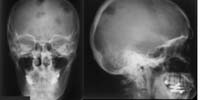

Skelettröntgen (RadioSurf) Interaktive Lernmodule zur Diagnostischen Radiologie des Skeletts für Studierende der Medizin public (öffentlich) Deutsch Studierende 1. Jahr | Studierende 2. Jahr | Studierende 3. Jahr | Studierende 4. Jahr | Studierende 5. Jahr | Studierende 6. Jahr | Ärztinnen/Ärzte in Weiterbildung Tutorial | Quiz | Mustererkennungstraining Website Anatomie

Anatomie (MorphoMed) Lernmodule zur Unterstützung verschiedener Kurse im Fach Anatomie:Sektionskurs, Schweineherzkurs, Neuroanatomiekurs, Radioanatomiekurs public (öffentlich) Englisch Studierende 1. Jahr | Studierende 2. Jahr | Studierende 3. Jahr Tutorial | Quiz | Mustererkennungstraining Website Anatomie

Skelettröntgen bei Kindern (PediRad) Lernprogramm zur Interpretation von Röntgenbildern des Bewegungsapparats bei Kindern public (öffentlich) Deutsch Studierende 4. Jahr | Studierende 5. Jahr | Studierende 6. Jahr | Ärztinnen/Ärzte in Weiterbildung Tutorial | Quiz | Mustererkennungstraining Website Pädiatrie